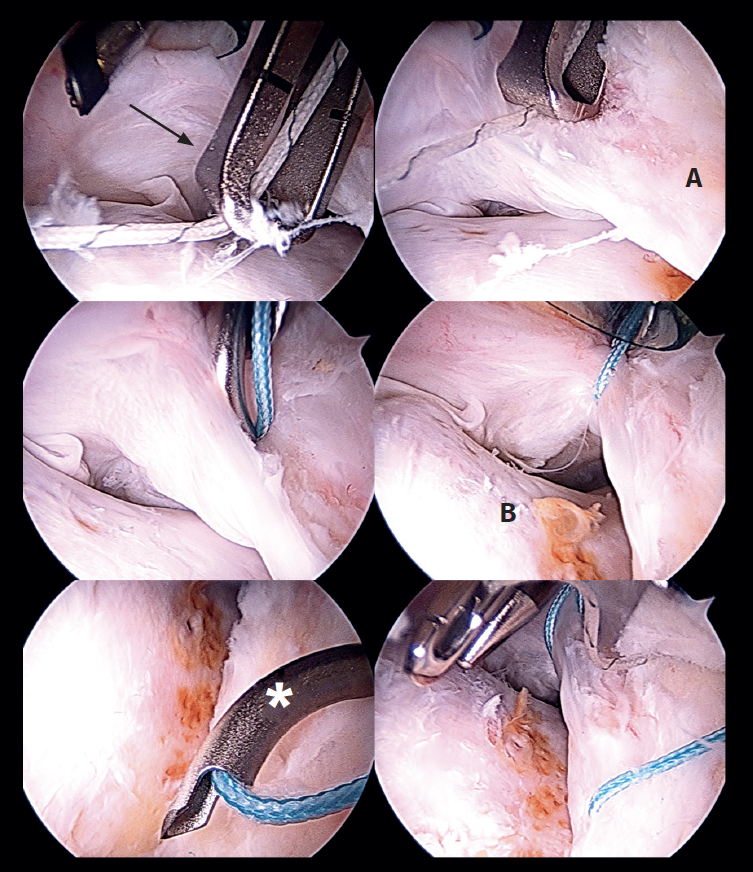

Introduction of the graft for labral reconstruction

Once all the sutures have been positioned, forceps are introduced from the posterolateral portal, taking care that they lie posterior to the last anchoring, with positioning within the joint. From the middle anterior portal we introduce the suture anchored to what will be the posterior part of the graft, likewise taking care that it lies anterior to the most anterior anchoring. This suture is retrieved from the posterolateral portal using the previously introduced forceps, applying traction to introduce the graft, and making it emerge through the posterolateral portal (Figure 6). At this point we fix the graft by passing sutures from the most anterior anchoring of the second row of anchorings, through the anterior part of the tibialis tendon, and it is then finally introduced and sutured. The sutures are then passed around the tendon graft in sequence, and are tightened little by little, maintaining traction from the posterolateral portal, and fixing and positioning the entire plasty from anterior to posterior (Figure 7). Once all these steps have been completed, the excess graft is radiofrequency amputated from the posterolateral portal.